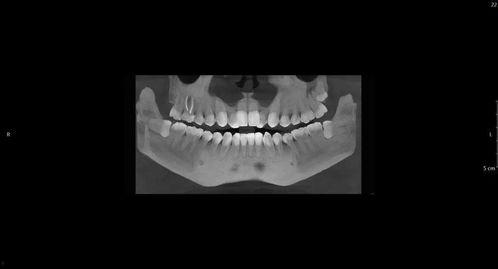

智齿的分布与形态

2021年的数据显示,智齿的分布情况因人而异。有些人长出了四颗智齿,而有些人可能一颗都没有。智齿的形态也各不相同,有的长得规规矩矩,有的却歪歪扭扭,甚至有的智齿长成了“倒钩”。

说到智齿,不得不提的就是疼痛。2021年,许多网友在社交媒体上分享了自己拔智齿的经历,其中不乏痛苦不堪的描述。智齿疼痛的原因有很多,比如智齿阻生、智齿发炎、智齿与邻牙拥挤等。